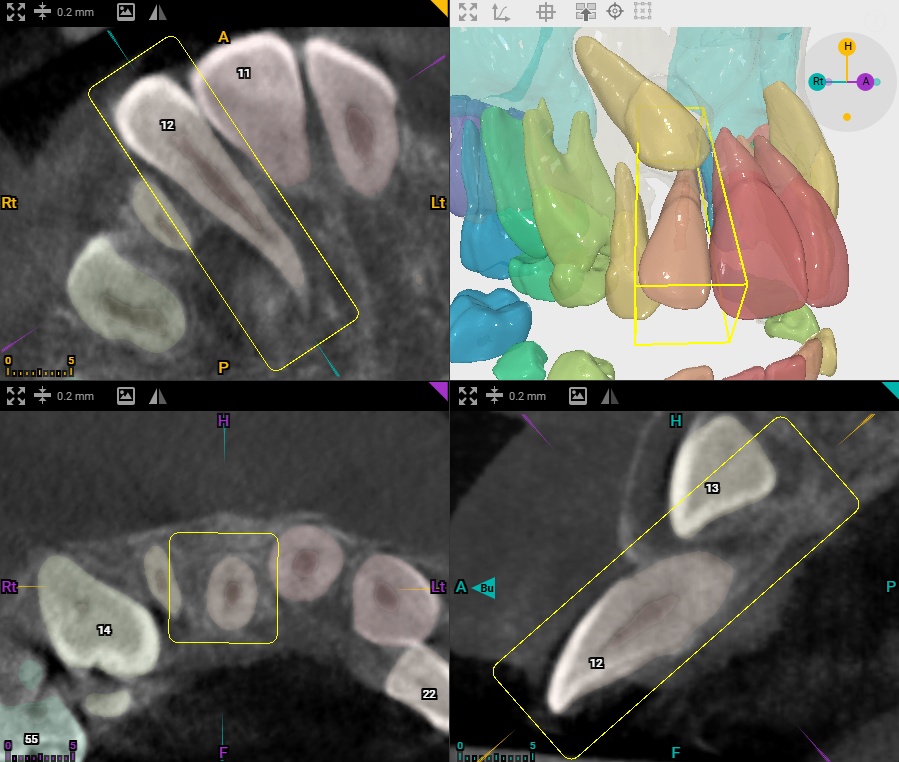

At Alliston Orthodontics & Oral Surgery, we believe that great results start with great diagnostics. That’s why we use advanced imaging tools like digital panoramic and cephalometric X-rays, iTero scanning, and 3D treatment planning to uncover issues that simply can’t be seen with the naked eye. From hidden impacted teeth to subtle jaw imbalances, our technology allows us to identify problems early, plan with precision, and avoid complications down the road.